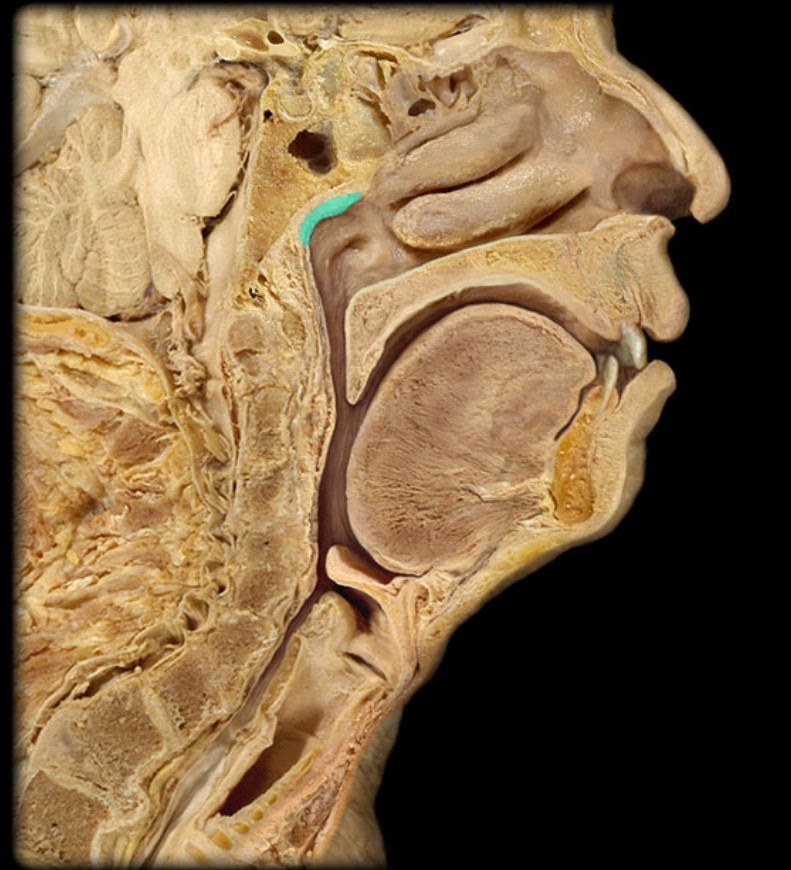

Pharyngeal Tonsil

21

New cards

Auditory Hiatus

22

New cards

Torus Tubarius

23